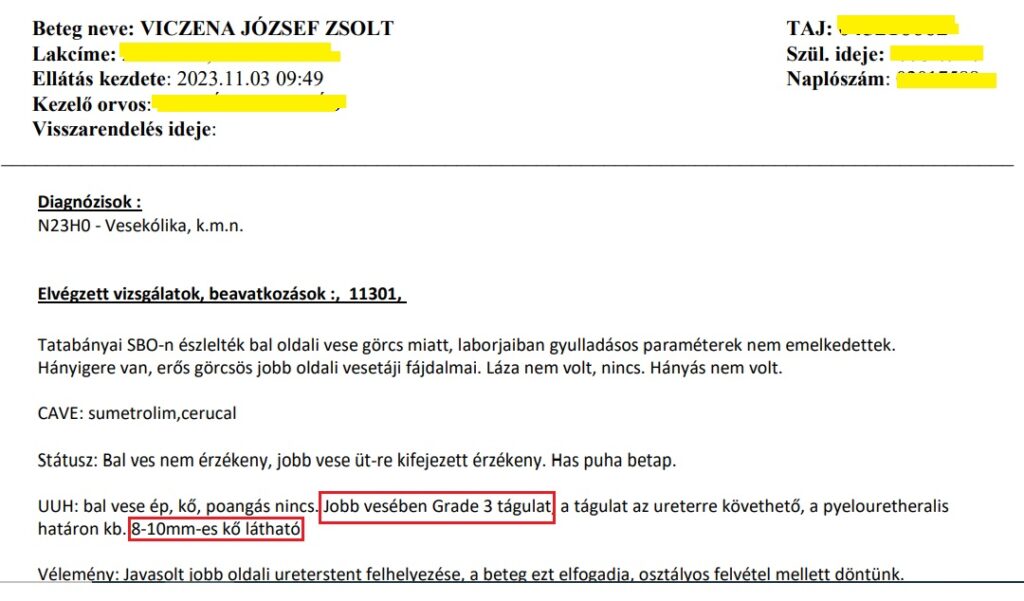

Tehát Zsoltnak 2023. október 30-án nagyon erős vesegörcsei lettek. Rögtön vesekövesség igazolódott 3 különböző ultrahang és 1 röntgen lelettel is, 3 különböző kórházban. A győri urológus az 8-10 mm-es követ és 3. fokozatú vesetágulatot diagnosztizált.

Zsolt befeküdt a győri Petz Aladár kórház urológiai osztályára úgy, hogy szeretett nagymamája, az édesanyám, éppen a megelőző napon hunyt el uroszepszisben – katéterekből eredő kórházi fertőzést, majd vérmérgezést kapott mindössze pár nap bennfekvés után Salgótarjáni kórházban. A fiam egyedül volt, mi éppen a teendőket intéztük Salgótarjánban. Aneszteziológus is jött hozzá, valami műtét előtti szokásos nyugtatót is kapott, aztán elmaradt minden. Orvost este 11-ig nem látott, vizit egy sem volt, a műtétből nem lett semmi, addig pedig hatásomra illetve megijedve az egésztől, a fiam úgy döntött sztentet nem vállal be. Este 11-kor eljött a győri kórházból úgy, hogy azt megbeszélte Dr Mosonyi Péterrel, aki alá is iratott vele egy lapot. A vesegörcsére szinte semmit nem használt amit ott adtak, a nospa-algopyrin infúziók 20 percre ha értek valamit és közölték náluk még Tramadol sincs, nem hogy erősebb fájdalomcsillapító a műtétig, felejtse el.

2023. November 16. Győr, Petz Aladár kórház, urológia:

A vesekőzúzást (ESWL) tágult, gyulladt vesén végezték. Az operációnál, mert hogy ez annak számít, nem volt jelen az orvos! (De később a papírt kiküldte Dr Mosonyi Péter egy kolléganőjével az orvosi szobából, ekkor már operatőrként aláírva!) Ezért a technikus és a nővér tanácstalanok voltak, mit tegyenek egy ilyen gyulladt, tágult vesével, amit ultrahanggal láttak, elvégezzék-e a beavatkozást. Végül a kőzúzás mellett döntöttek. A fiam veséje az egyik legnagyobb mennyiséget, 3000-es ütésszámot kapta! Három hét múlva a fiam észrevette, hogy vérvizelése van. Odaadta az edényt, hogy vigyem le a háziorvosához, Dr Reisz Kornéliához, hogy adjon egy beutalót rá, hogy gyorsan le tudjuk adni. Megtagadta a beutalót, azt mondta, majd az asszisztens tesztcsíkkal megnézi. Aki pedig azt állapította meg, hogy „nincs benne vér, picike fehérje, de vér nincs.” A fiam otthon felrobbant a hülyének nézéstől, felöltözött és a már akkor is rossz állapotában maga vitte el a tatabányai Synlab-hoz leadni ugyanezt a vizeletet. A „nincs vér” igazából 3 keresztes vérvizelés és 100-szoros vörösvörtest/látótér volt. Már ekkor elkezdődött az, amiből aztán ahogy a cikk címe is utal rá, egy horrortörténet lett!